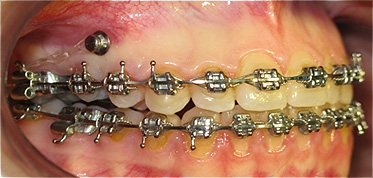

Apinhamento dentário com os dentes caninos em desoclusão (classe II, divisão 2).

![]() |

Após dois anos de tratamento ortodôntico.